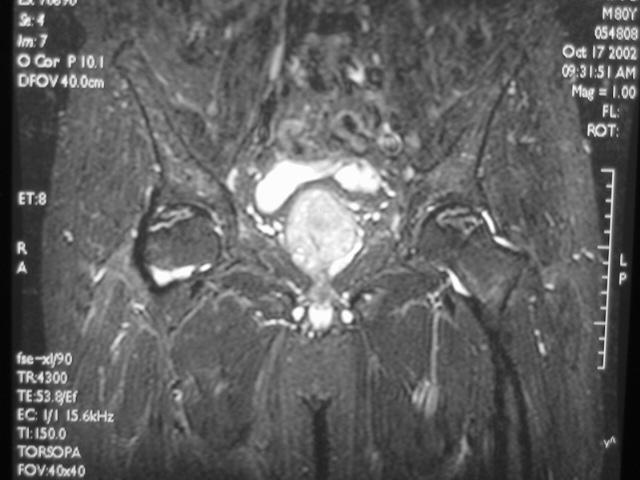

MRI诊断

Ⅱ期

髋关节间隙正常,股骨头光整、不变形。

在T1W上,股骨头前上部负重区,有硬化缘围绕较低、不均匀信号的新月形坏死区。

在T2W上,病灶为星月形高信号区。

在X线平片上,股骨头负重区内可见高密度的硬化区,内可伴有小囊样改变。